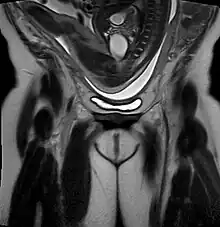

- Fetal size in relation to maternal pelvic size – If the mother's pelvis is roomy and the baby is not large, this is favorable for vaginal breech delivery. However, prenatal estimates of the size of the baby and the size of the pelvis are unreliable.[28]

- Hyperextension of the fetal head – this can be evaluated with ultrasound. Less than 5% of breech babies have their heads in the "star-gazing" position, the face looking straight upwards and the back of the head resting against the back of the neck. Caesarean delivery is absolutely necessary because vaginal birth with the baby's head in this position confers a high risk of spinal cord trauma and death.[28]